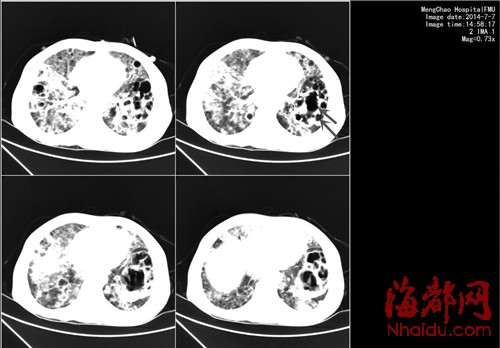

肺部CT显示肺部已经被“腐蚀”出一个个空洞(如箭头所示)

2个月前,黄萍突然发烧,还咳嗽,咳出黄色的浓痰并伴有气促。她在莆田当地医院挂了三天的抗生素,还是高烧40℃,后被转诊到福建医科大学附一医院,她的肺部CT片子显示出一个又一个空洞,大的有橘子(6厘米×7厘米)大小,小的也有圣女果(3厘米×2厘米)大小。